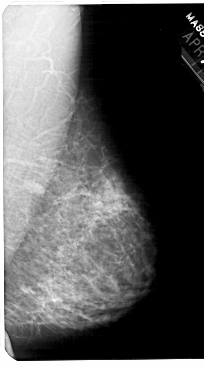

A_1777_1.RIGHT_MLO

RIGHT_MLO LINES 5491 PIXELS_PER_LINE 3046 BITS_PER_PIXEL 12 RESOLUTION 43.5 NON_OVERLAY